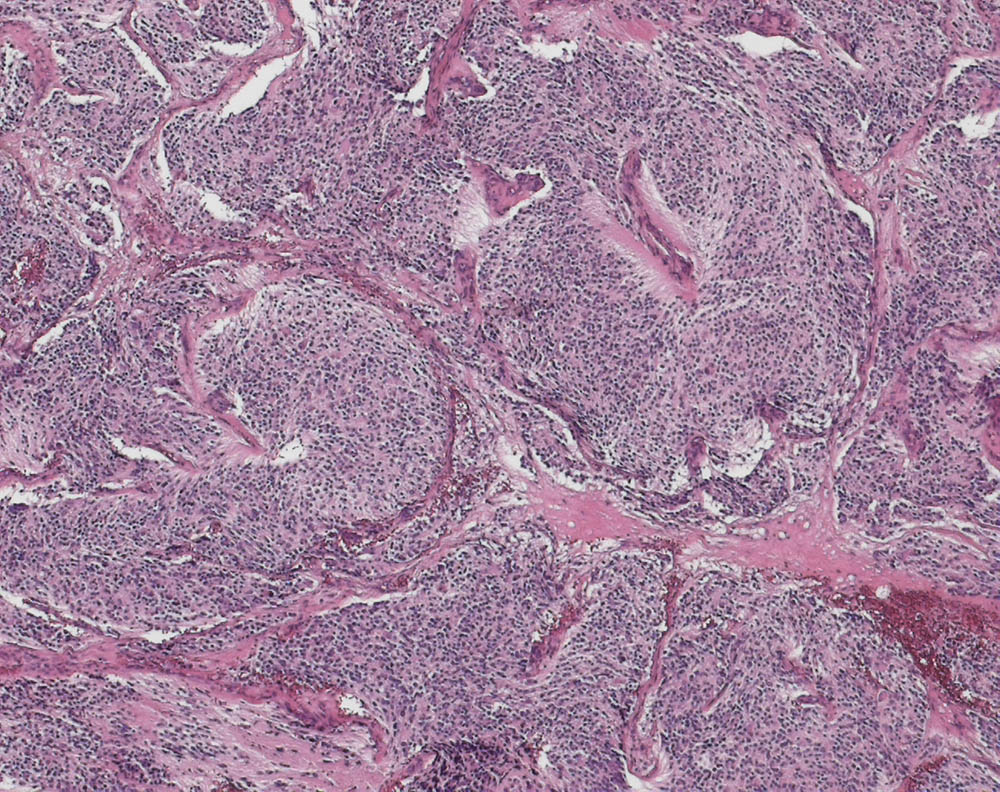

Wenig differenziertes Neuroblastom

Epiduralraum

Monotoner Zellrasen kleiner zytoplasmaarmer Zellen mit runden Kernen. Die Zellrasen werden von fibrovaskulären Septen durchzogen. Wenig fibrilläres Stroma.

Neuroblastom, schwannzellstromaarm, wenig differenzierter Subtyp, nach der INPC-Klassifikation: Niedriger Mitose-Karyorrhexisindex. Neuroblastom Grad III nach Hughes.

Epiduraler Tumor BWK 7/8. DD: Metastase, Plasmozytom.